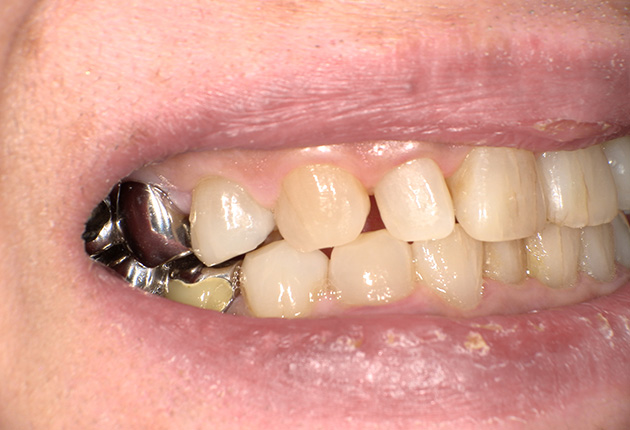

よく噛めず笑うと銀歯が目立つので気にされていました。

| 主訴 | ブリッジ脱離、しっかり噛めない |

| 診査診断 | 上顎歯牙欠損、歯周病、不良補綴、根尖性周囲炎。 不正咬合により噛み合わせのバランスが悪い事が原因により咬合治療が必要。 |